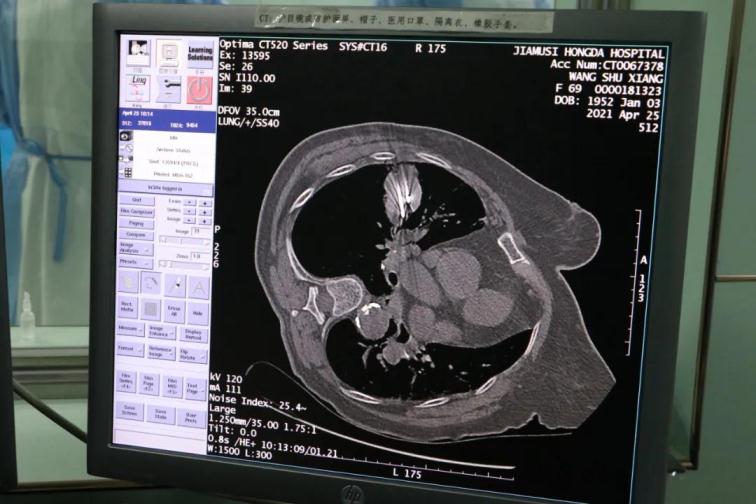

為了提高CT影像下肺腫瘤定位的精準度,術(shù)前胸外科團隊聯(lián)合CT影像科趙文禮主任和董明鑫醫(yī)師詳細研究了肺CT定位方案,采取國際上先進的CT網(wǎng)格定位法,對肺腫瘤精確定位,定位精度可達5mm以內(nèi)。經(jīng)過團隊合作充分準備后對肺癌實施了氬氦刀穿刺治療,微創(chuàng)穿刺針孔3mm,局麻鎮(zhèn)痛,分段治療40分鐘。病人全程在韋文康護士長護理團隊心肺監(jiān)測下進行,確保了手術(shù)安全。

氬氦刀治療后即刻CT評價肺腫瘤核心密度下降,手術(shù)后5天CT評價肺癌與周圍正常肺組織對比,水腫帶形成,癌組織出現(xiàn)壞死。治療取得了良好效果。遠期效果需要繼續(xù)隨訪觀察。病人手術(shù)后1周無并發(fā)癥痊愈出院。